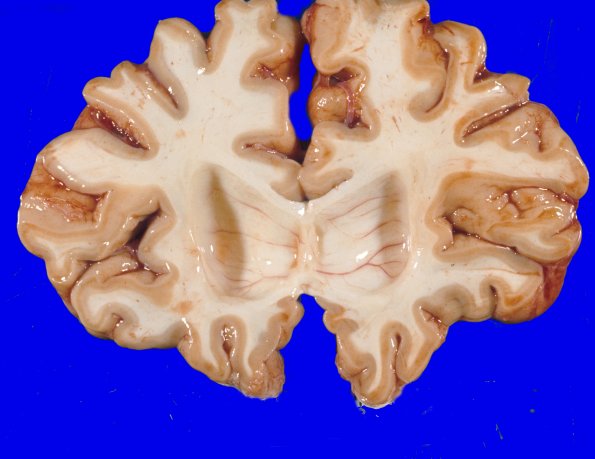

Coronal sections of the cerebral hemispheres and deep gray nuclei appear atrophic with dilatation and blunting of the lateral ventricles.